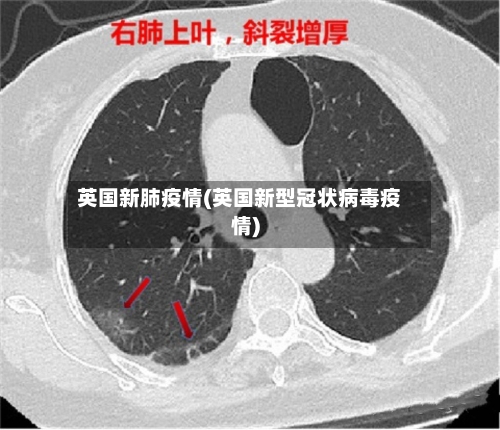

英国新肺疫情(英国新型冠状病毒疫情)

英国70岁以上新冠感染者占比创纪录,这个国家的疫情发展到什么程度了...

英国国家统计局的数据显示 ,英国各地感染新冠肺炎病毒的人数创历史新高 。其中,70岁以上感染者比例达到6%,创下新的历史纪录。据此前报道 ,英国国家统计局新冠肺炎疫情调查项目高级统计师卡拉表示,奥密克戎亚型突变株BA.2在英国各地的传播导致感染人数迅速增加。